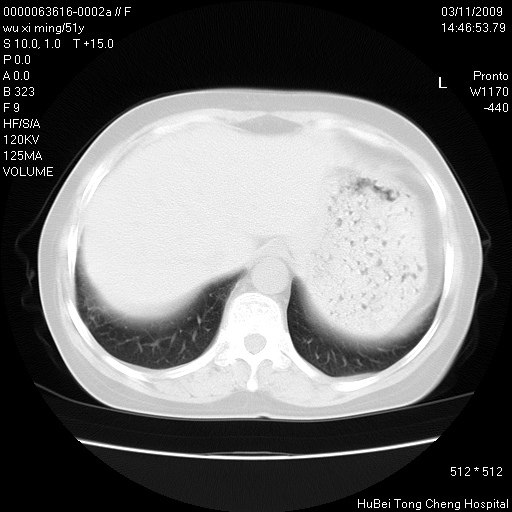

患者 女,51岁。因“胆囊炎,胆囊结石”,行常规术前胸部x线检查发现:右上肺结节病灶,建议行进一步检查。患者无咳嗽、咳痰及咯血等呼吸道症状,近期出现背部疼痛不适。

胸部ct轴位平扫(层厚10mm,螺距1.5,重建间隔10mm;部分层面:层厚3mm,螺距1.0,重建间隔3mm),图像如下:

右肺周围型肺癌伴肺内转移信胸椎转移

1、周围型肺癌。(毛刺正、血管束集征,分叶。)

集束征,胸膜牽拉征,毛刺,淺分葉高度提示ca.

右肺周围型肺癌伴肺内转移及胸椎转移。已无手术机会。